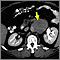

A needle biopsy involves inserting a needle into a lymph node. This type of biopsy can be performed by a radiologist with local anesthesia, using ultrasound or CT scan to find the node. It can also be performed by a surgeon without imaging if the lymph node can be felt.